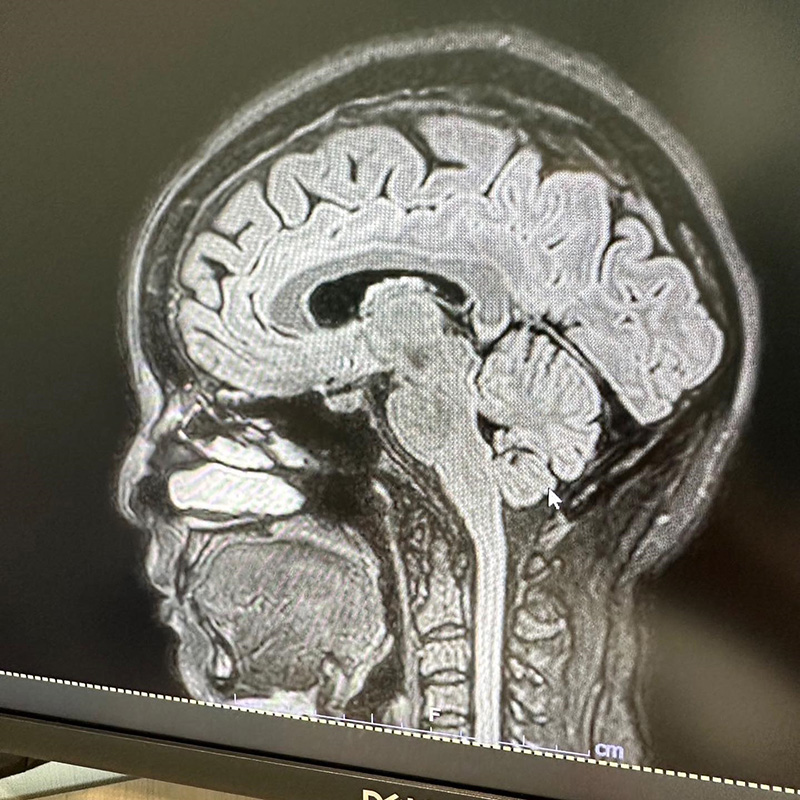

ตั๊ก บงกช เผยภาพ MRI สมอง ทำหลายคนเป็นห่วง เผยทำเพราะปวดหัวมาก นึกว่าเป็นเนื้องอก ก่อนพบเป็นไมเกรน ต้องฉีดยาอีก 3-6 เดือน

ทำเอาหลายคนเห็นแล้วอดเป็นห่วงไม่ได้ เมื่อล่าสุด (9 พฤศจิกายน 2566) ตั๊ก บงกช ได้เผยภาพ MRI สมอง ลงใน IG จนคนสงสัยว่าเกิดอะไรขึ้น ป่วยเป็นอะไรหรือเปล่า ซึ่งเจ้าตัวก็ได้บอกเล่าที่มาที่ไปของภาพนี้ว่า....

"MRI สมอง เพราะปวดหัวมาก สรุปเป็นไมเกรน นึกว่าเป็นเนื้องอก ลุ้นแทบตาย โล่งอก คุณหมอให้ยาฉีดที่ขาแต่เป็นยาฉีดสำหรับไมเกรน ดีขึ้นเลย แต่ต้องฉีดต่อเนื่อง 3-6 เดือน ดีจังไม่ต้องทนปวดกินยาแล้ว"